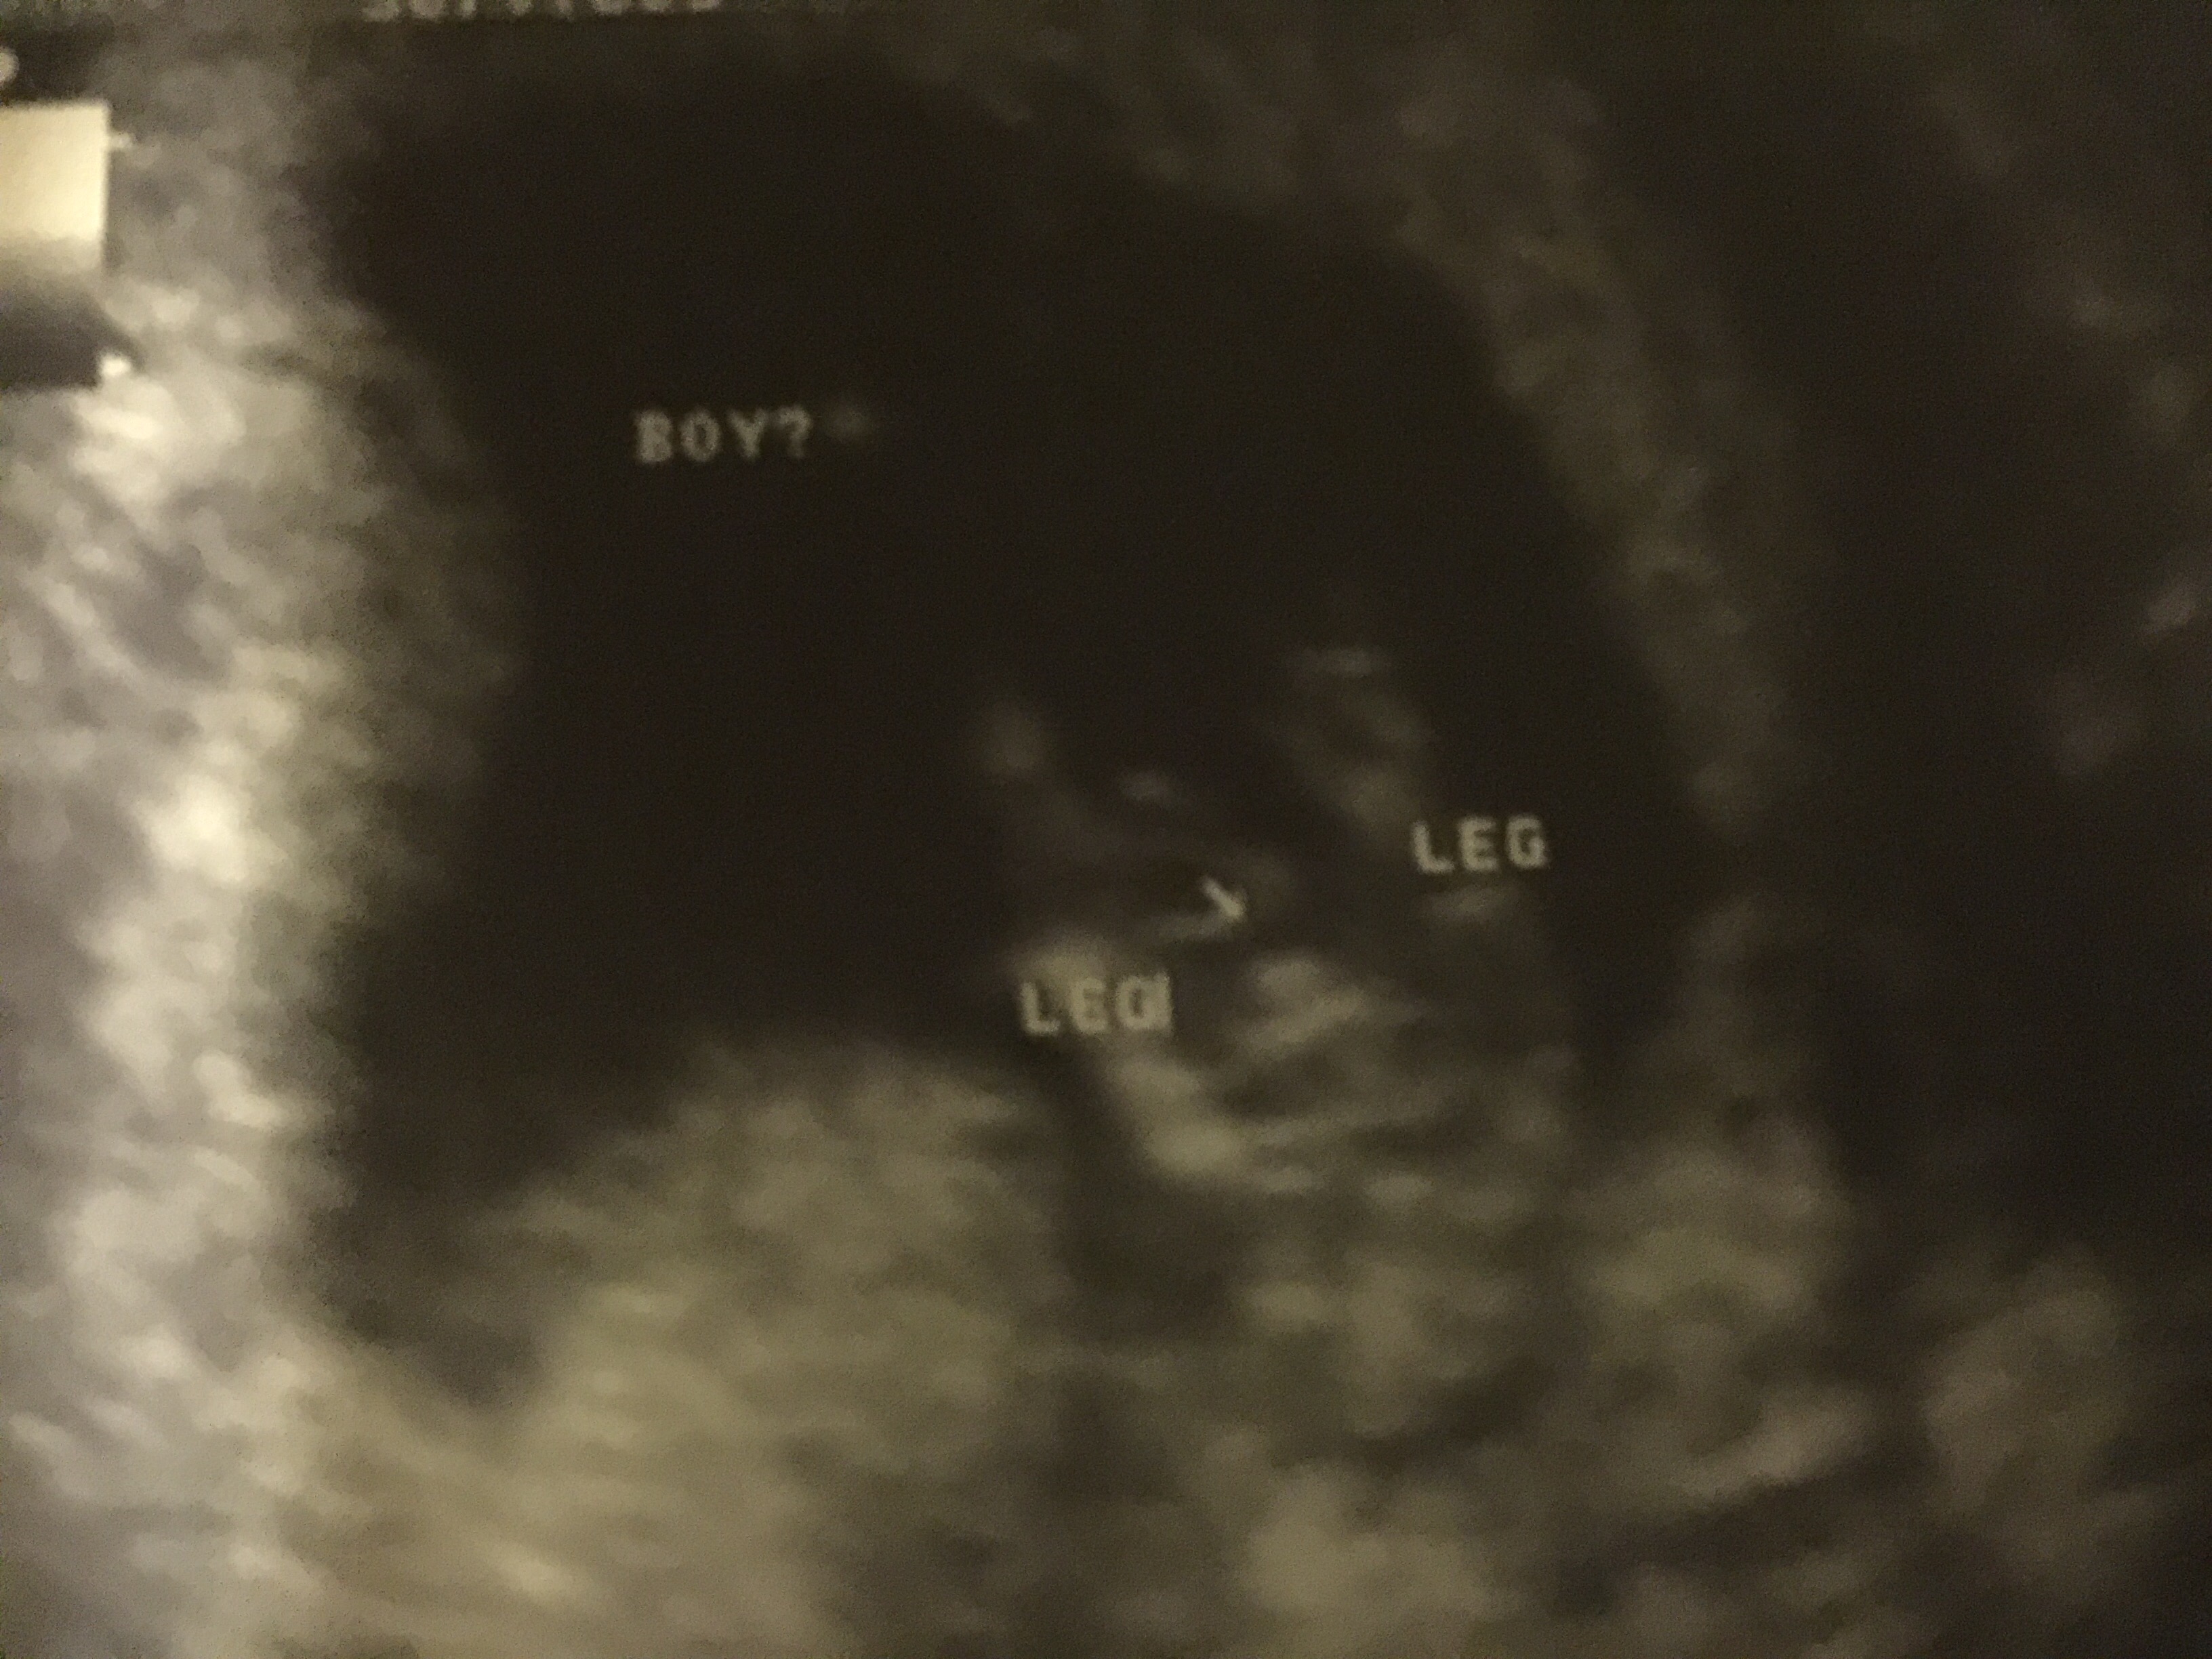

Hello I'm new here I just got an ultrasound done yesterday tech was 100 % boy what do you guys think ??Attachment 28467

looks like a boy

boy!

Looks boyish but definitely wait for your next scan to confirm :)